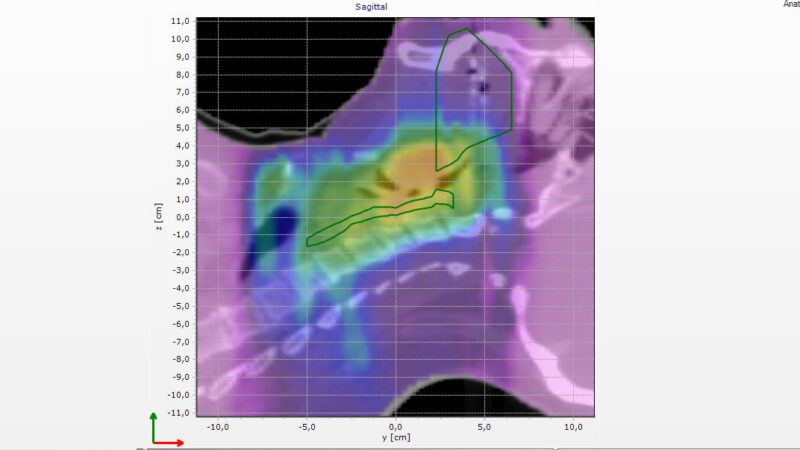

With the Delta4DVH Anatomy software option, you can verify and analyze the dose that has been delivered to the patient anatomy. Based on the measurements in the isocentric target region and dose calculation of the dose in the patient anatomy you now have a truly independent verification of the delivered dose.

Analyze the dose delivered to the patient anatomy